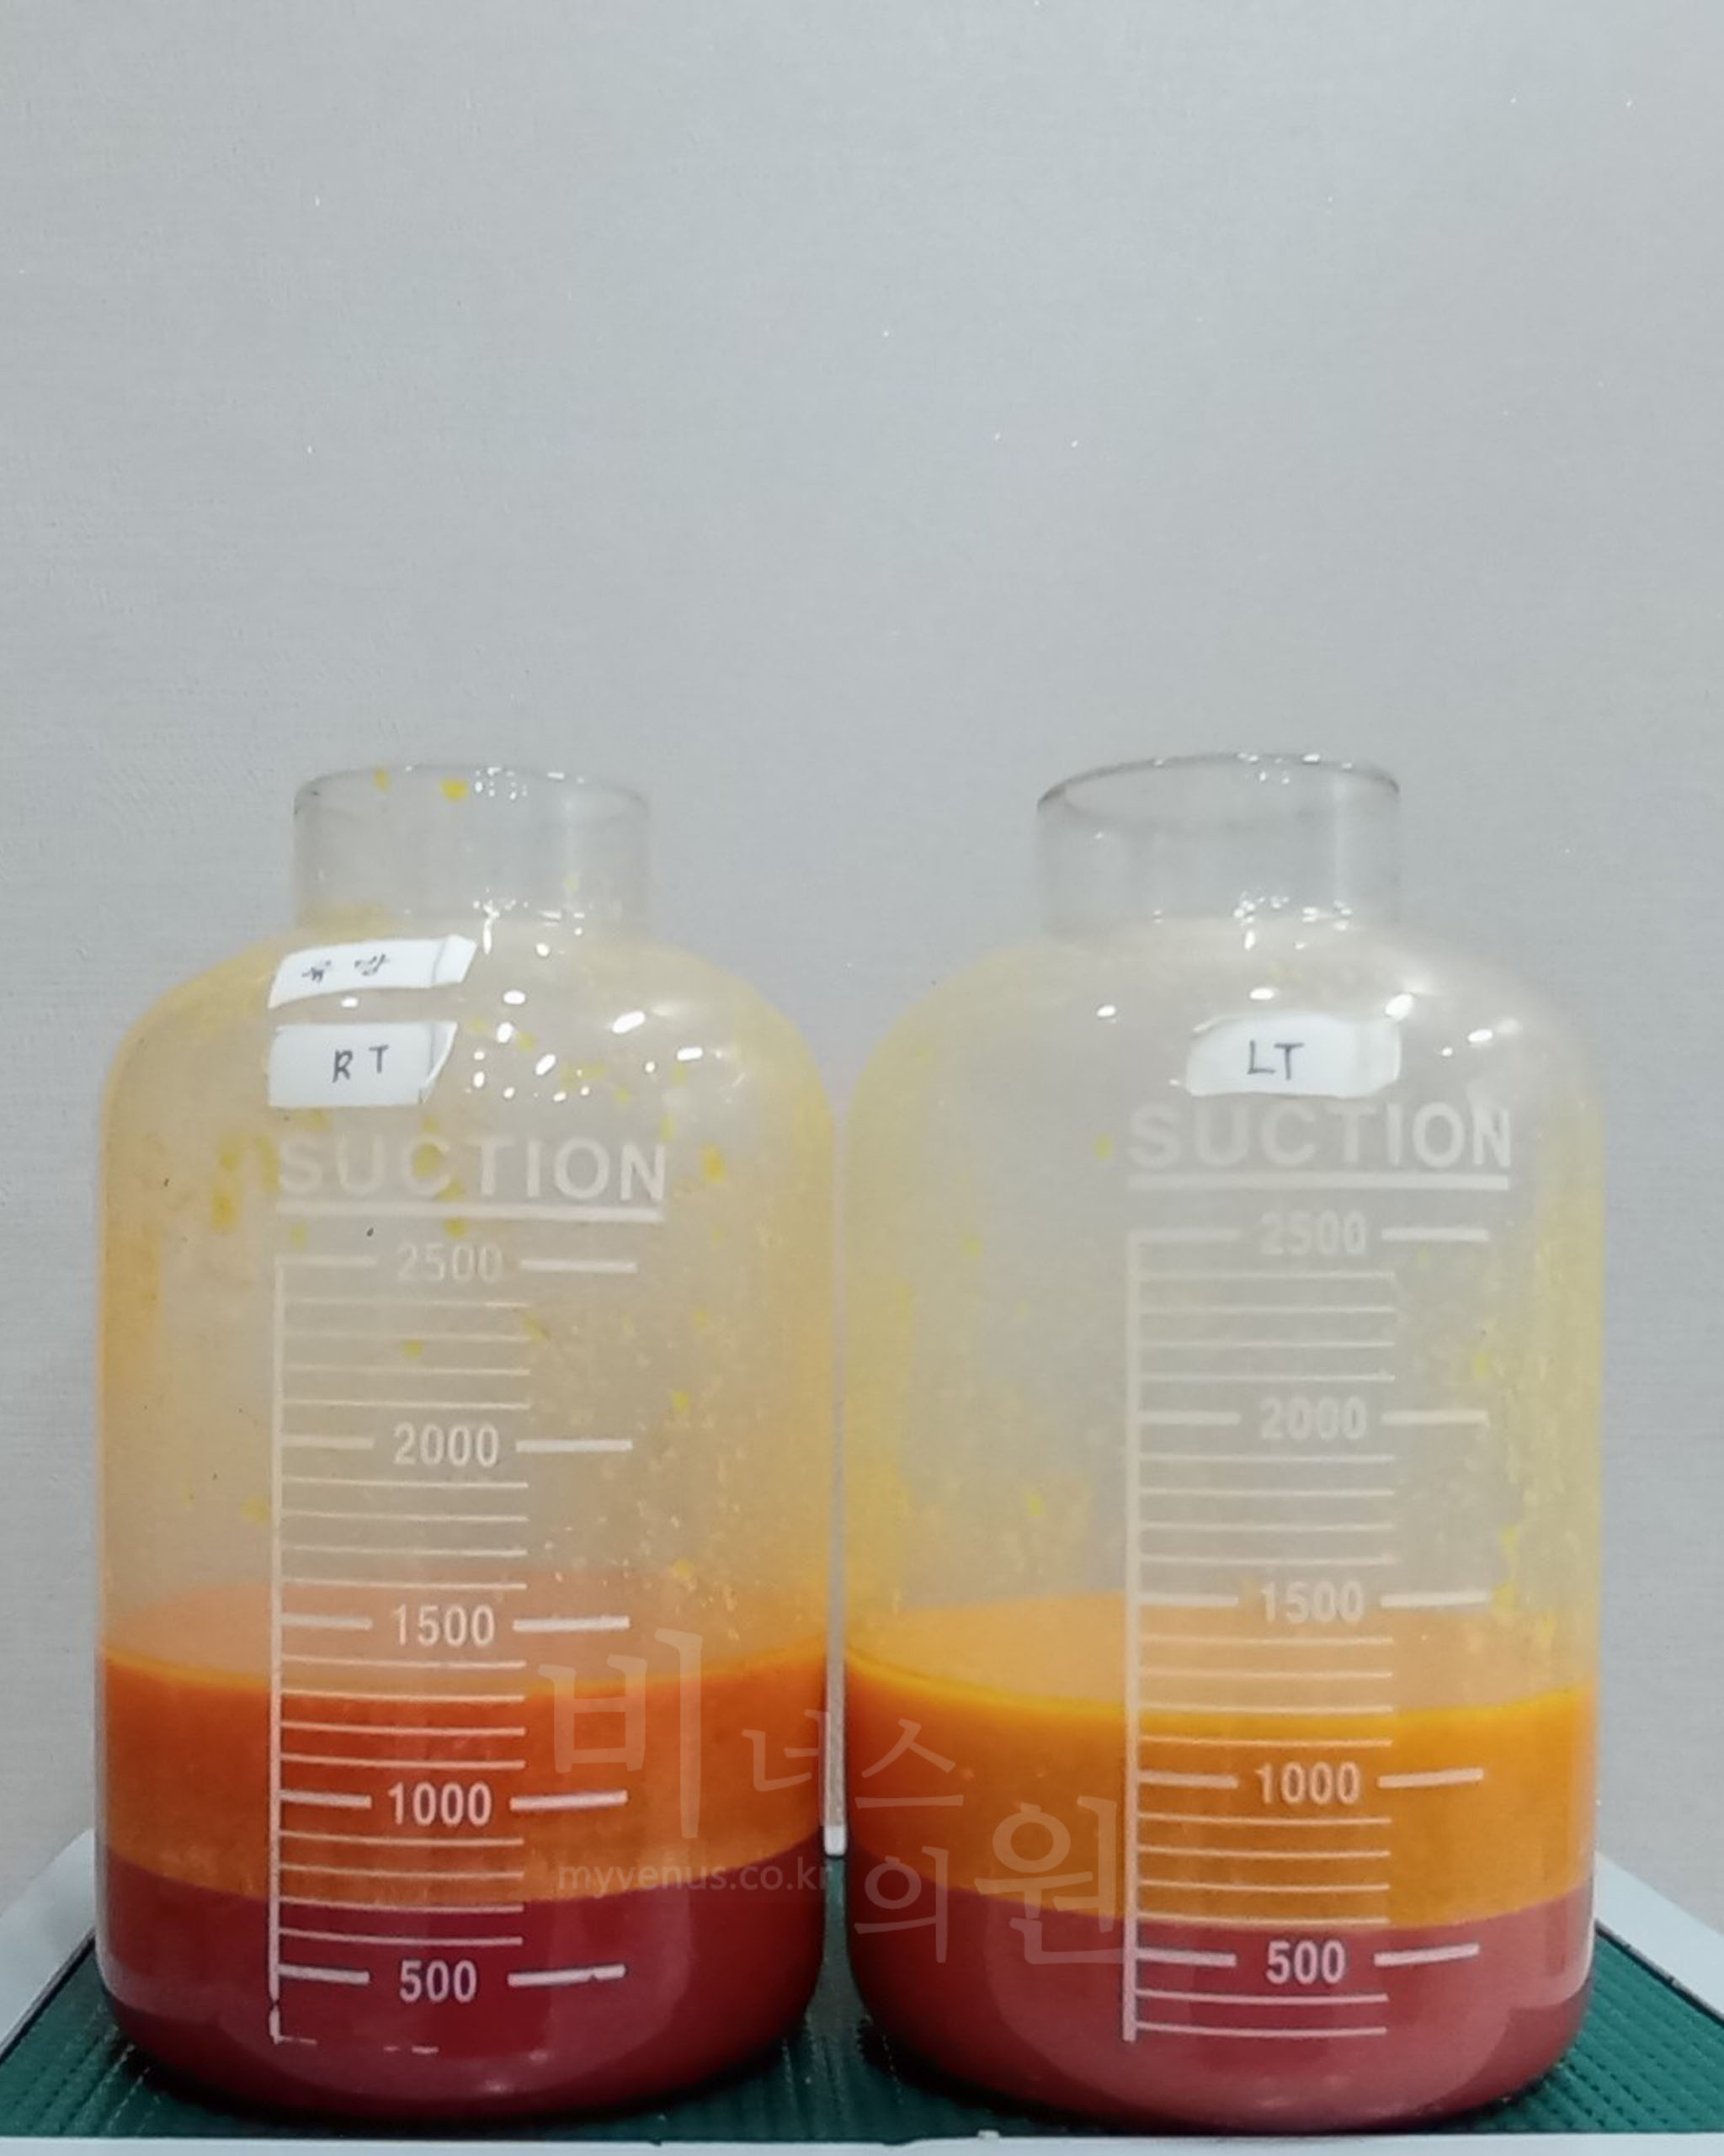

지방흡입을 통한 가슴축소 지방량

노란 지방량이 흡입된 모습

절개법의 경우 지방층 뿐만 아닌 유선 조직을 잘라내야 하는 경우도 있으므로 수유장애 등의 위험도도 있을 수 있지만, 가슴 지방흡입의 경우 지방만을 흡입하기 때문에 향후 분만 계획이 있거나 미혼 여성에게는 권해드릴 수 있는 큰 장점이 있어요.